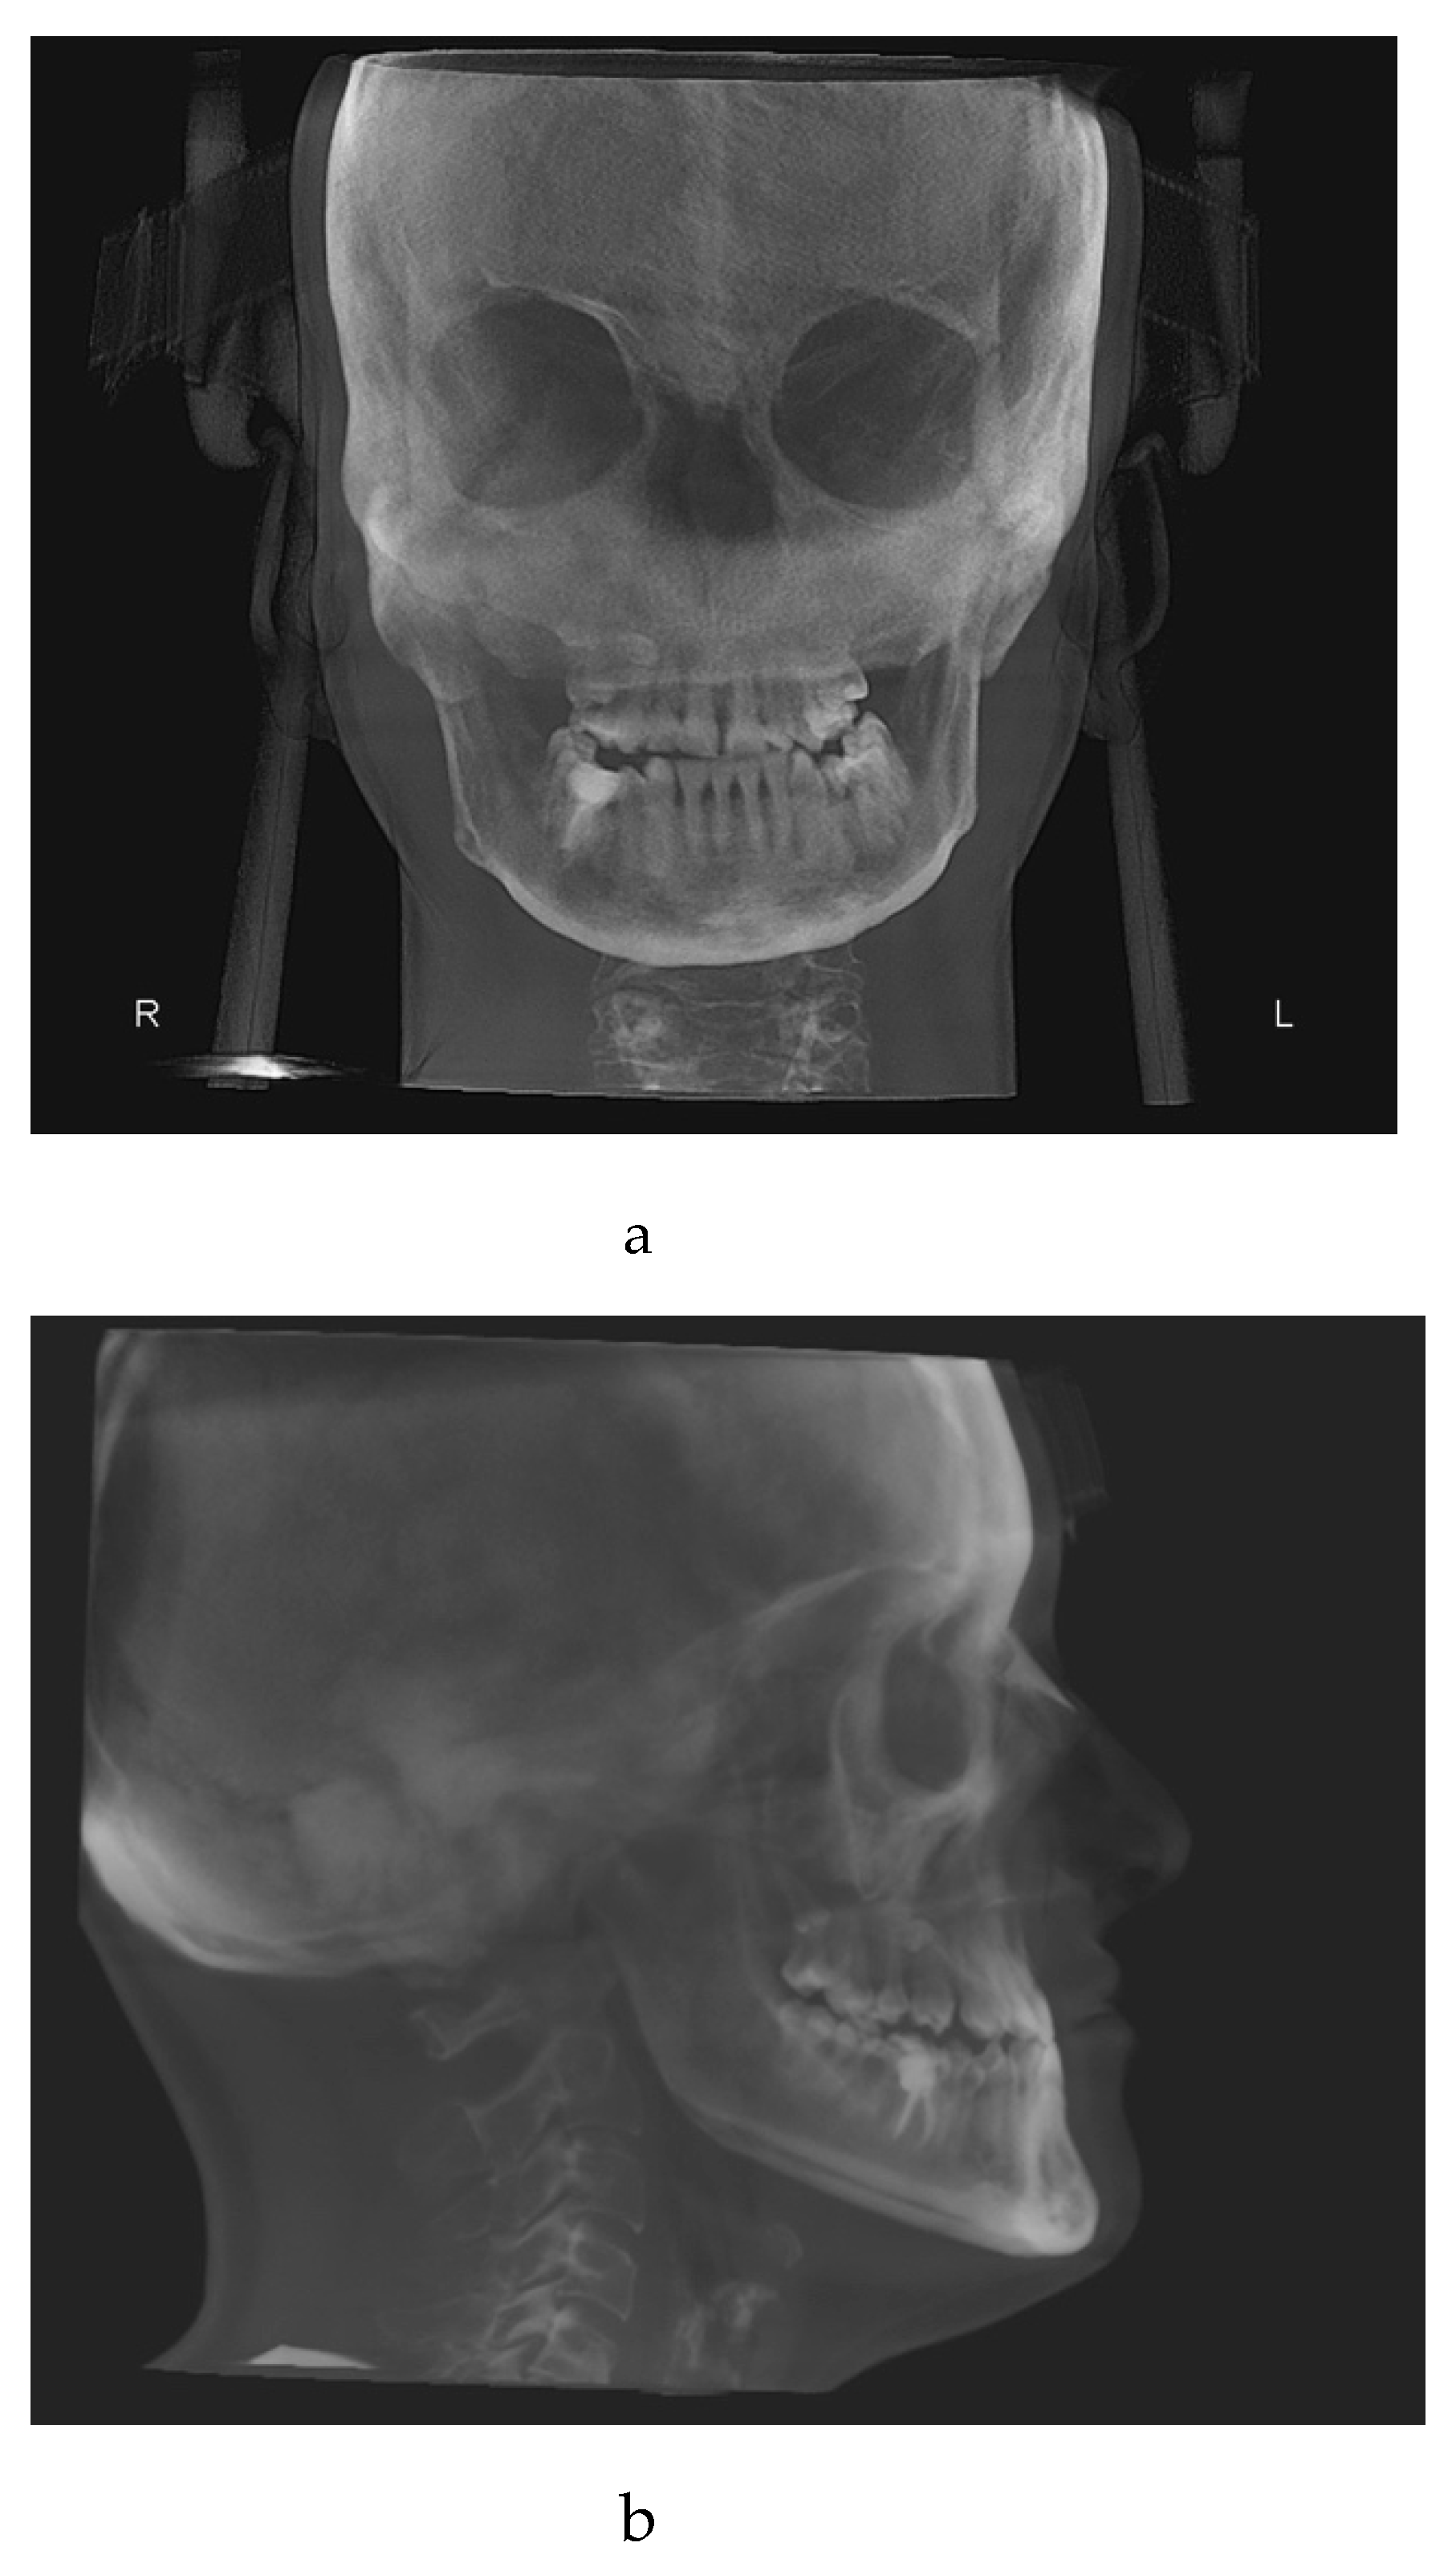

The x-ray examination through cone beam computed tomography (CBCT) [22] (Figure 1a, 1b, 1c) processed with dolphin software [23] showed:

- Third skeletal class

- Hyperdivergent skeletal profile

- Left lateral deviation of the mandible

- Contracted upper arch

- Inclusion of 15 in a transverse position, near the apexes of elements 1.4 and 1.6.

Figure 1. a: antero-posterior projection of the CBCT. b: lateral-lateral projection of the CBCT. c: panoramic projection of the CBCT.